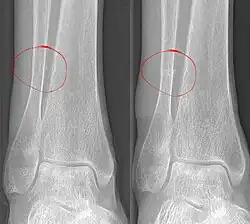

Als Okkulte Fraktur bezeichnet man einen Knochenbruch (Fraktur), der in der normalen Röntgenaufnahme nicht erkennbar oder nicht direkt erkennbar ist. In einigen Fällen können indirekte Frakturzeichen auf das Vorhandensein einer Fraktur hinweisen, in anderen Fällen ist allein anhand des Röntgenbildes der Bruch überhaupt nicht erkennbar. Bei entsprechendem Verdacht – zum Beispiel aufgrund von heftigen Schmerzen – kann dann in den meisten Fällen eine Magnetresonanztomographie (MRT) oder eine Computertomographie (CT) den Bruch zeigen oder ausschließen. Bei Patienten, für die z. B. wegen eines Herzschrittmachers eine MRT nicht in Frage kommt, kann auch eine Skelettszintigraphie zum Frakturnachweis durchgeführt werden.

Auch in nach Tagen bis Wochen angefertigten Röntgenaufnahmen kann eine zunächst okkulte Fraktur sichtbar werden. Es zeigen sich dann die Reaktionen des Körpers auf den Knochenbruch wie Verminderung der Knochendichte am Bruchspalt durch Resorption oder Verdickungen oder Verkalkungen der Knochenhaut im Rahmen der Knochenbruchheilung. Im ungünstigeren Fall kommt es doch noch zu einer Verschiebung der Knochenbruchstücke gegeneinander, so dass der Frakturspalt direkt sichtbar wird.